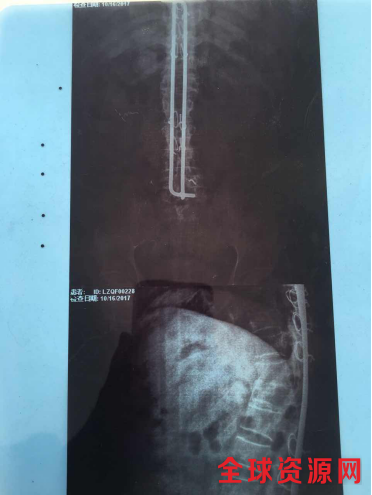

脊椎钢针影像资料

时经22年后,战友们亲眼目睹了刘沛建受伤后的真实情况是,后背从颈部到尾椎骨有一条近70公分长的刀疤缝合口,两根固定脊椎骨钢针从肩膀直接贯穿到臀部,并且臀部的创口一直未能愈合。

他有严重的脑震荡后遗症,长期头痛,伤口一直处于发炎状态,大小便失禁和尿血,需长期服用镇痛药、镇静药、消炎药等才能缓解身体多处的病痛。每天都要更换尿布多次,每次伤口都需要碘酒、消炎药膏纱布、药棉进行伤口处理。每月看病用药最低要千元以上,每月房租近百元,去除以上两项开支,无力维持日常开销,生活费用都要靠亲朋好友的援助和借债来维持。22年来无时无刻都处在病痛的折磨之中,挣扎在死亡线上;贯穿脊椎骨的钢针让他夜不能寐,臀部的创口和腿部的踝骨坏死让他无法坐和立;他的生是一种精神顽强的表现。